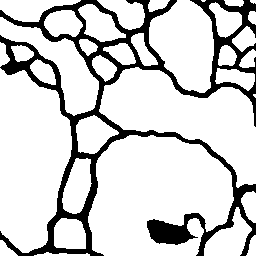

Vessel Extraction

Experiments are implemented on the Digital Retinal Images for Vessel Extraction database (DRIVE) proposed for studies on the extraction of blood vessels (Staal et al. 2004). Models are trained after reshaping all data at 256256 size. Rand score and information theoretic score is also used as evaluation metrics.

The following provides quantitative comparisons of three FCNs respectively. Example results on various image-to-image mapping tasks are shown in Figure 2.

Table 2 lists the best evaluation results. It shows that our model performs on par with U-Net and better than FCN-16s.